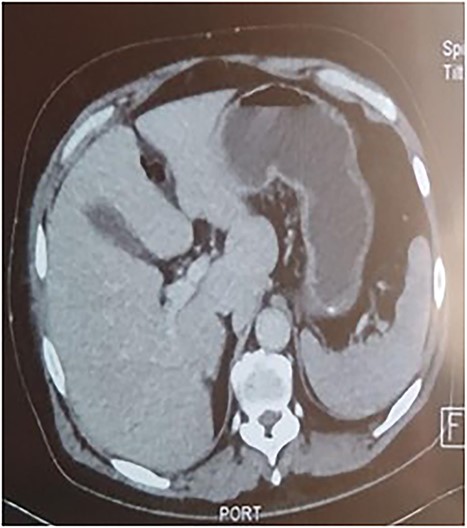

A 53-year-old man with no known medical history was admitted to the hospital because of epigastric pain persisting for 24 h, accompanied by weakness. Physical examination revealed a temperature of 39°C, severe dehydration, poor peripheral perfusion, a pulse of 110 bpm, blood pressure at 10/6 mm/Hg, a painful and tympanic abdomen without peristalsis, with tenderness over the epigastric region. Laboratory tests showed a lipase level of 667 U/l, sodium at 140 mmol/l, potassium at 4.5 mmol/l, creatinine at 106 μmol/l, urea at 6.5 mmol/l, alanine aminotransferase at 161 U/l, aspartate aminotransferase at 85 U/l, an elevated leukocyte count at 29,3 × 109/l. Abdominal CT with contrast revealed pancreatic necrosis with gas surrounding the pancreas, as well as pneumoperitoneum and in the right anterior pararenal space. Thickening of the mesentery root with lymph node enlargement (Figs 1–3).

In our case, CT plays a significant role in therapeutic management, and the presence of extra-digestive gas motivates the surgical indication [1, 3, 6].